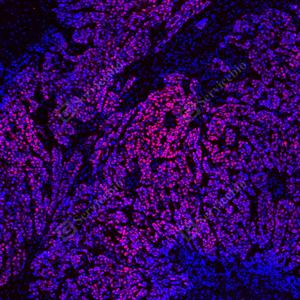

| IF检测p53蛋白(货号 GB151740)(红色). 样品: 人结肠癌, 4%多聚甲醛 (货号G1101) 固定12-24小时. 抗原修复: Tris-EDTA抗原修复液(pH 9.0) (G1203), 100℃, 25分钟. 封闭: 3% BSA(货号GC305010)的PBS溶液, 室温孵育30分钟. —抗: 1: 1500稀释, 4℃ 孵育过夜. 二抗: Cy3标记山羊抗小鼠IgG (H+L) (货号GB21301), 1: 300稀释, 室温孵育1小时. |